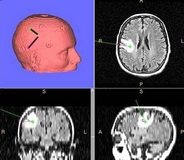

Sistemin hazırlanması 15 dakika sürüyor

Nöronavigasyonun yönteminin çalışma sistemi hakkında bilgi veren Doç. Dr. Tucer, sözlerini şöyle noktaladı: “Operasyon öncesinde hastanın BT veya MR çekimleri yapılıyor. Bir veya daha fazla görüntüleme yöntemi ihtiyaca göre aynı anda kullanılabiliyor. Çekilen bu görüntüler, nöronavigasyonun bilgisayar ünitesine transfer ediliyor. Navigasyon planlama bilgisayarında görüntüler işlendikten sonra ameliyathanedeki üniteye aktarılıyor. Bu görüntüler, sisteme 3 farklı yöntemle tanımlanabiliyor. Yüzeysel belirleyicilerle, anatomik landmarkerlarla veya Z-touch dediğimiz cihazla yüz taraması uygulanarak yapılıyor. Cilt insizyonu ve lezyona uygun merkezli kraniyotomi planlanıyor, nöronavigasyona cerrahi mikroskop ve ultrasound da tanımlanarak cerrahiye başlanıyor. Nöronavigasyon hazırlığı ve planlanması ortalama 15 dakika sürüyor.”